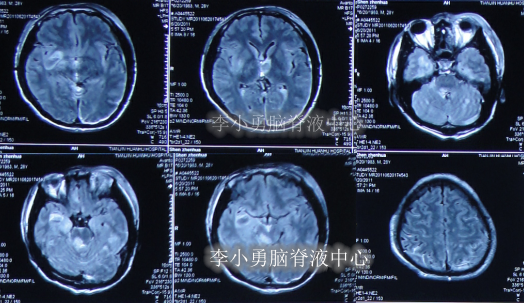

在第2家医院治疗2个月后转至第3家医院天津某军队医院,分别于2012年2月21日和2012年5月23日进行了干细胞移植,其中在第3家医院治疗前曾查头部MRI示脑室仍扩张(图-11)。

图-11:2012年2月22日头部MRI

在第3家治疗半年的时间内,继续给予高压氧治疗,但病情仍未见好转,且不断加重:频繁间断高热,意识模糊,大小便失禁,肢体刺激后才有反应,其中于2012年9月4日查头部MRI示仍脑积水(图-12)。

图-12:2012年9月4日头部MRI